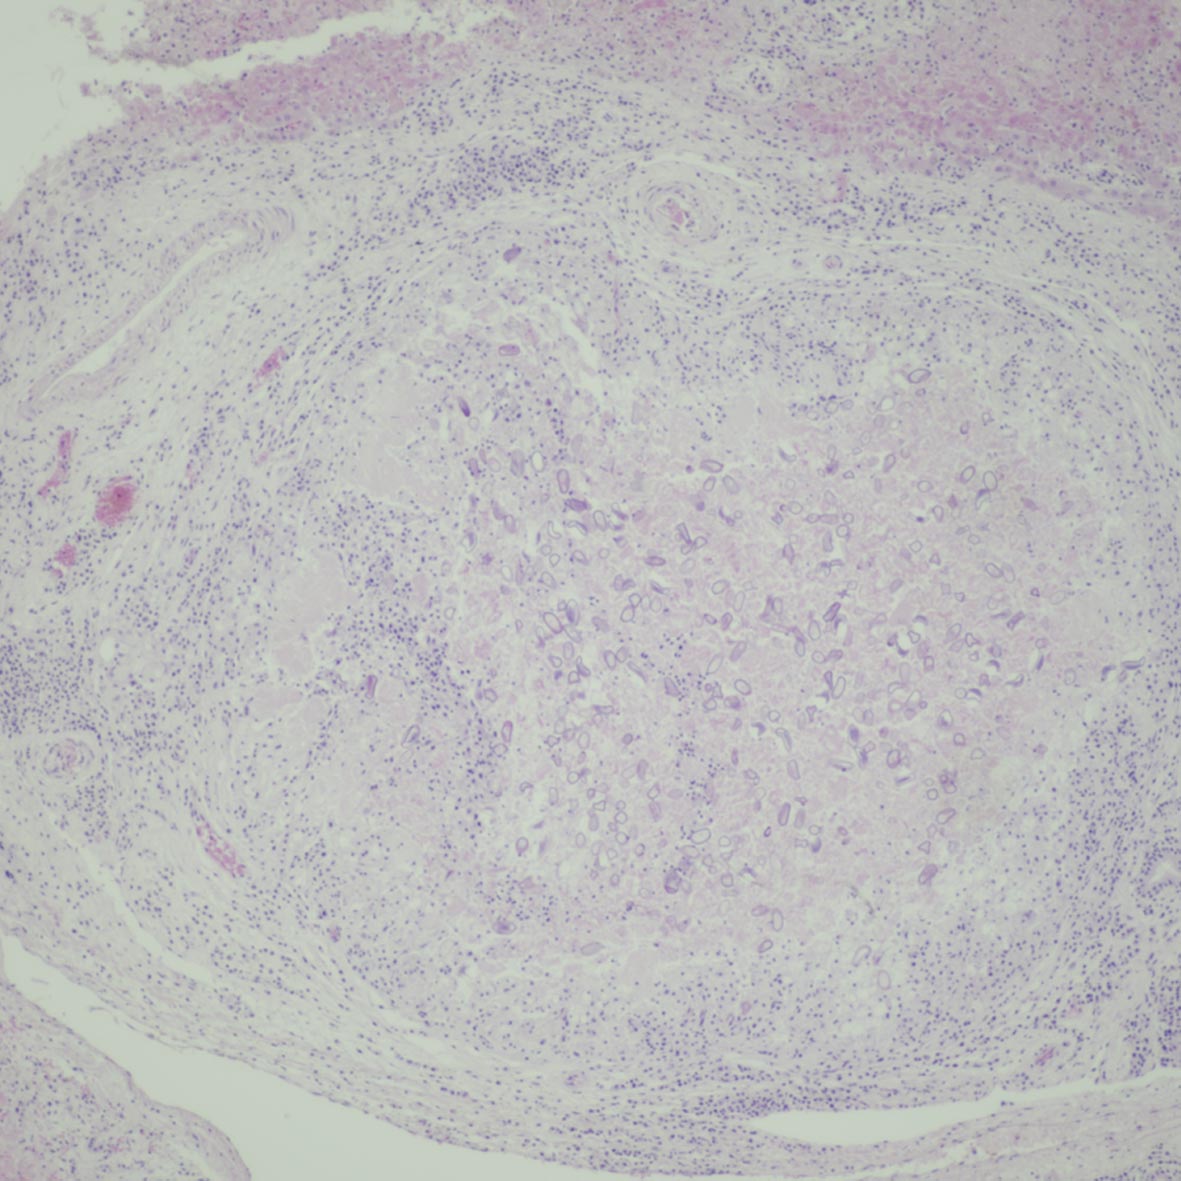

Hepatic coccidiosis

A low power view of hepatic coccidiosis. The rabbit died from RHD2 and this was a coincidental finding